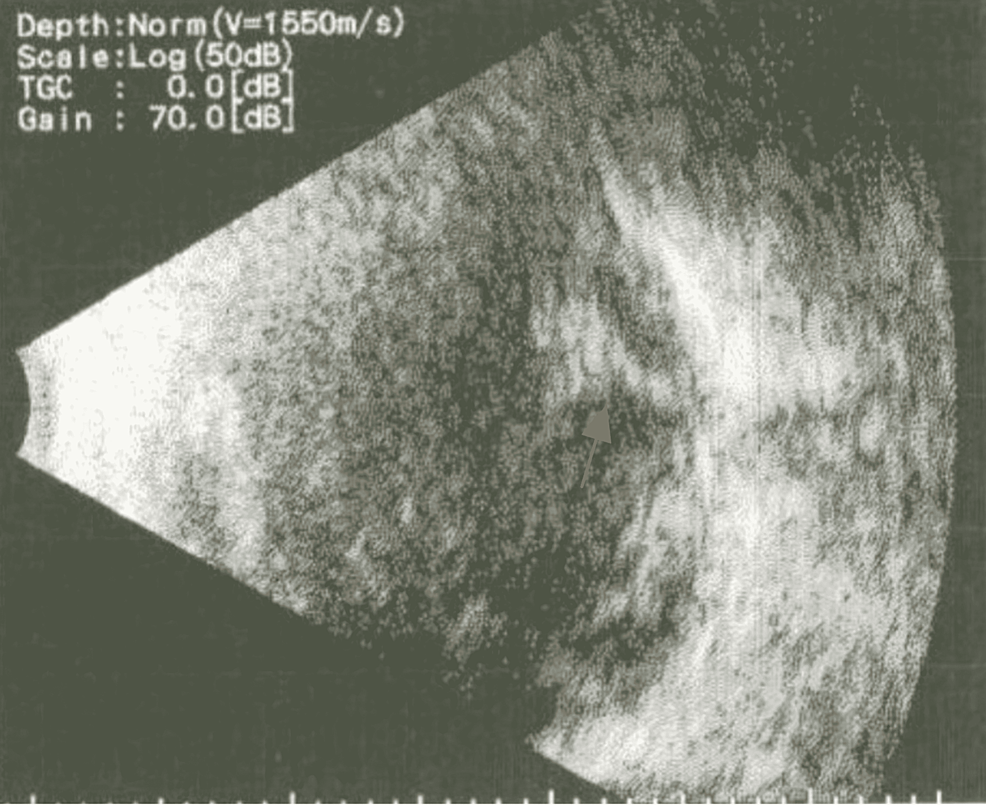

From webeye.ophth.uiowa.edu

Atlas Entry Optic disc hemorrhage in normal tension Optic Nerve Eye Hemorrhage the authors reviewed 93 consecutive cases with optic disc swelling (ods) to compare clinical manifestations. to characterize changes in the retinal nerve fiber layer (rnfl) and peripapillary vessel density (vd) at the. The oct rnfl image doesn’t identify disc hemorrhage. a disc hemorrhage was defined as a hemorrhage within one disc diameter of the optic nerve. . Optic Nerve Eye Hemorrhage.